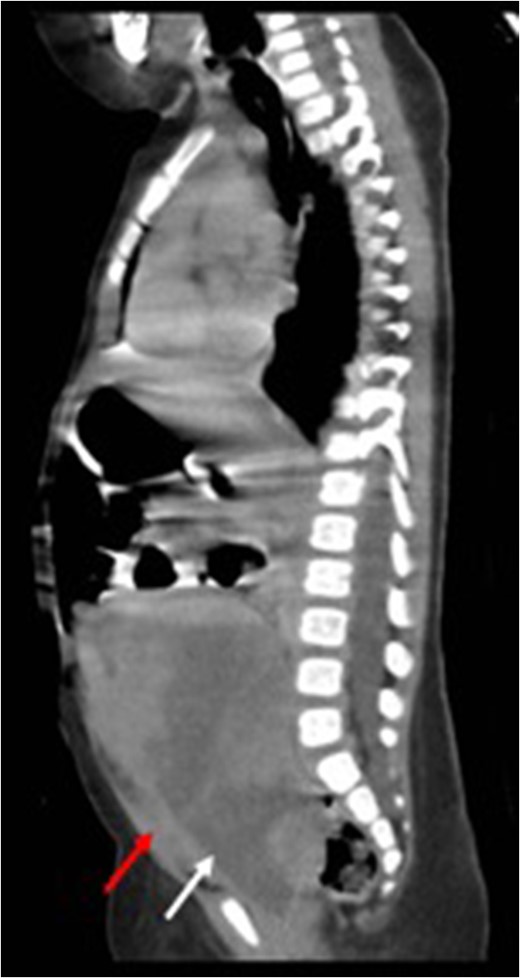

Before treatment sagittal view (CT) showing a large mass (white arrow) compressing on bladder (red arrow).